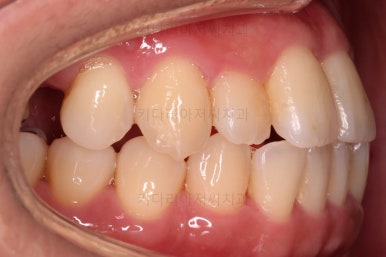

초진 시, 입안의 모습이에요.

결손부위가 눈에 띄고요.

결손부위가 양쪽에 있다보니 윗니 중간에 틈새가 벌어졌네요.

뒤쪽의 빈공간으로 치아들이 도미노처럼 쓰러져서 그렇습니다.

앞니의 약간의 틈새, 약간의 삐뚤어짐, 약간의 중앙선 틀어짐 등 심하진 않으나 약간씩의 문제점들이 있네요.